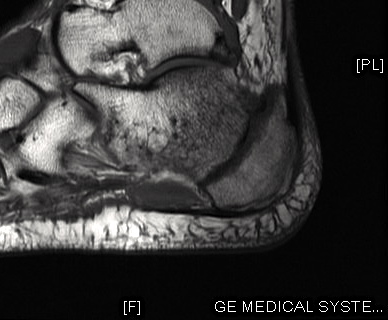

To cut then an even longer story short, I discovered afterwards, following first X-rays and then an MRI scan, that I had what in the medical field is termed bilateral calcaneus fractures. To the layman (which includes me) that means “two broken heels”. To boot I have a torn tendon just below my right ankle, and the right foot is considerably more sore than the left, as perhaps is illustrated more clearly by the pictures below, which are from the MRI scan:

Towards the right of the above picture you will see that the heel bone has basically split – the back part is apparently separated from the remainder. That might explain why it hurt so much! As if to add insult to injury, I also have post-traumatic arthritis in my left heel, and the torn tendon in my right.